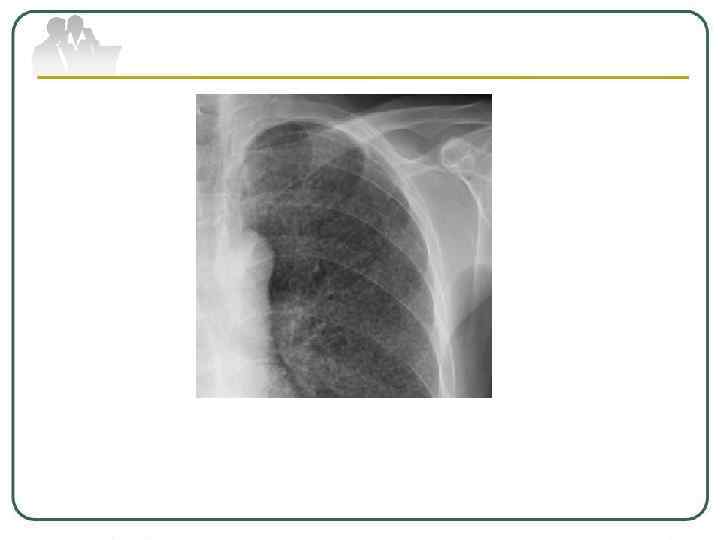

Туберкулема легких - понятие, объединяющее разнообразные по генезу инкапсулированные казеозные фокусы величиной более 1, 0 см в диаметре. Различают туберкулемы иифильтративно-пневмонического типа, гомогенные, слоистые, конгломератные и так называемые "псевдотуберкулемы" - заполненные каверны. На рентгенограмме туберкулемы выявляются в виде тени округлой формы с четкими контурами. В фокусе может определяться серповидное просветление за счет распада, иногда перифокальное воспаление и небольшое количество бронхогенных очагов, а также участки обызвествления.